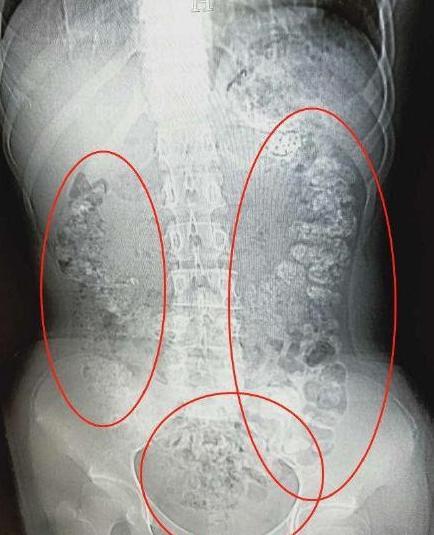

前些日子,小沈突然肚子疼,而且最近5天都无法排便,吃不下东西。她赶紧跑到医院去挂了急诊,结果照了个CT发现,她的胃肠道里,布满高密度颗粒状阴影,疑似珍珠奶茶里的“珍珠”,估计有百余颗。paz灵异岛|www.lingyidao.com